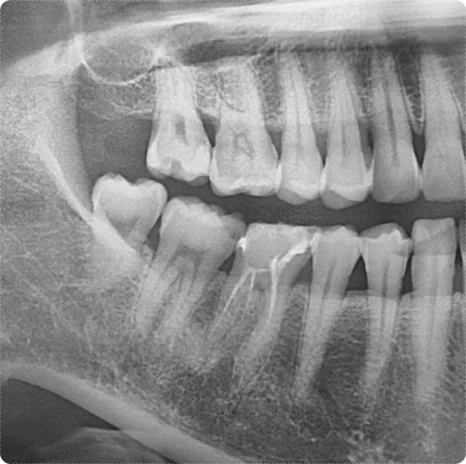

첫 번째 환자분은 치아에 미세한 균열이 있었지만 뚜렷한 통증은 없었습니다.

임시치아를 한 달 정도 사용해 보면서 경과를 확인한 후, 크라운 치료를 진행했습니다.

결과적으로 치아를 보호하면서 튼튼하게 회복할 수 있었고, 환자분도 만족해하셨습니다.